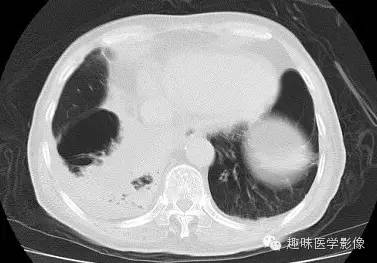

双肺多发无壁低密度区,以右肺下叶底部为主。右肺下叶见大片不规则实变阴影伴多发空洞影,实变肺组织内见支气管气象,右肺下叶支气管局部显示不清。纵隔内见淋巴结。右侧胸腔内见积液影,邻近胸膜肥厚。主动脉、冠状动脉钙化。

右肺下叶肺脓肿、肺炎伴胸腔积液,肺气肿、肺大泡。

右胸廓变小,心影右移;右肺下叶多房性空洞,空洞内未见明显液平面,右下肺病变应该是下叶阻塞性肺炎,实变肺组织内见支气管气像,邻近胸膜增厚,并合并胸腔积液,支持肺脓肿。